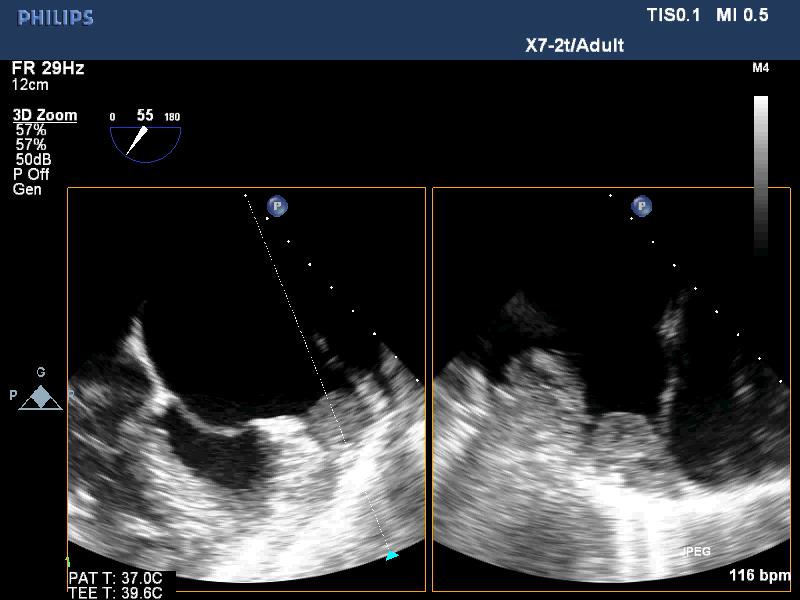

Figure 2. LA thrombus on 3 D TEE; “TEE image from Nguyen Tuan Vu”

Figure 3. Normal LAA on TEE; “TEE image from Nguyen Tuan Vu”

Figure 4. Thrombus in LAA on 3D TEE; “TEE image from Nguyen Tuan Vu”

TTE identifies the disease. TEE detects spontaneous contrast and thrombi in LA, LAA of patients with mitral stenosis. It is important to decide using anticoagulation before percutaneous balloon mitral valvuloplasty or surgery (Figures 1-8).